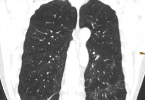

Erster hochauflösender Einzelzell-Atlas zum Lungenkarzinom

COVID-19 und das Risiko für anhaltende Lungenveränderungen